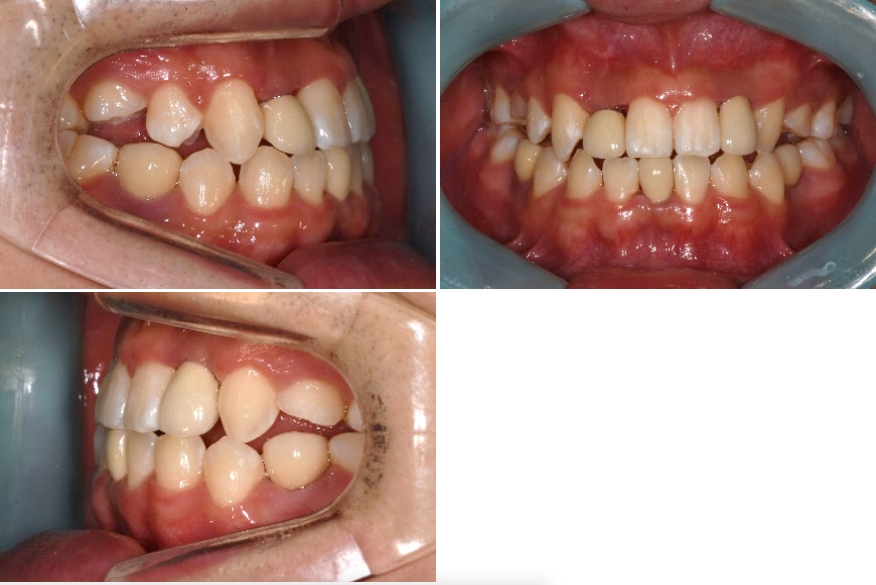

충분한 양의 측절치 공간 확보후 임플란트 식립및 보철로 치료를 마무리하였습니 다. 치근이동이 원활히됨으로 인해 임플란트 식립하기 충분한 공간이 확보되었으며 중절치의 전방이동으로 반대교합이 해소되었습니다.

부분교정은 고정원 문제의 해결여부에 따라 전체교정에 비해 쉬울 수도 혹은 더 어 려울 수도 있으므로 임플란트 공간 확보를 위한 교정치료시 이를 고려하는 것이 필수적이라 하겠습니다.

임플란트 보철치료가 완료된 후 생길 수 있는 잔여접촉점 사이의 공간 폐쇄를 위해 다시 교정의에게 의뢰하였습니다. 선천적 결손 부위인 하악 양측 제2소구치의 경우 하방의 골밀도는 일반적으로 떨어져 있는 경우가 많습니다.